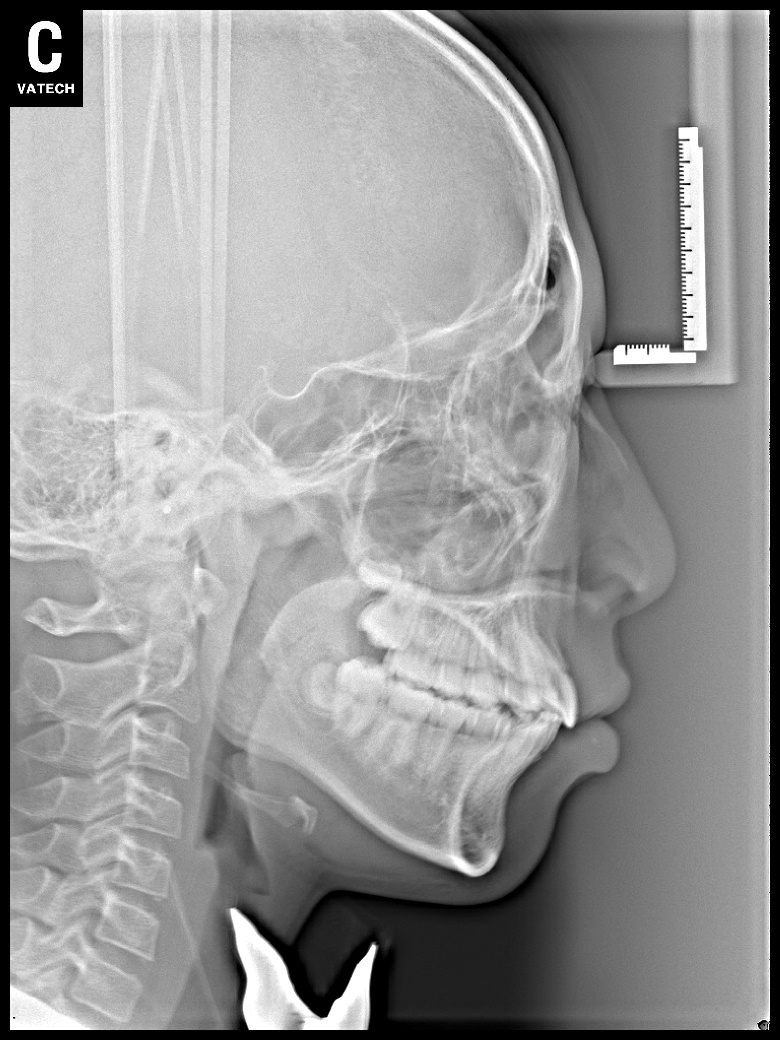

치료 전 사진입니다.